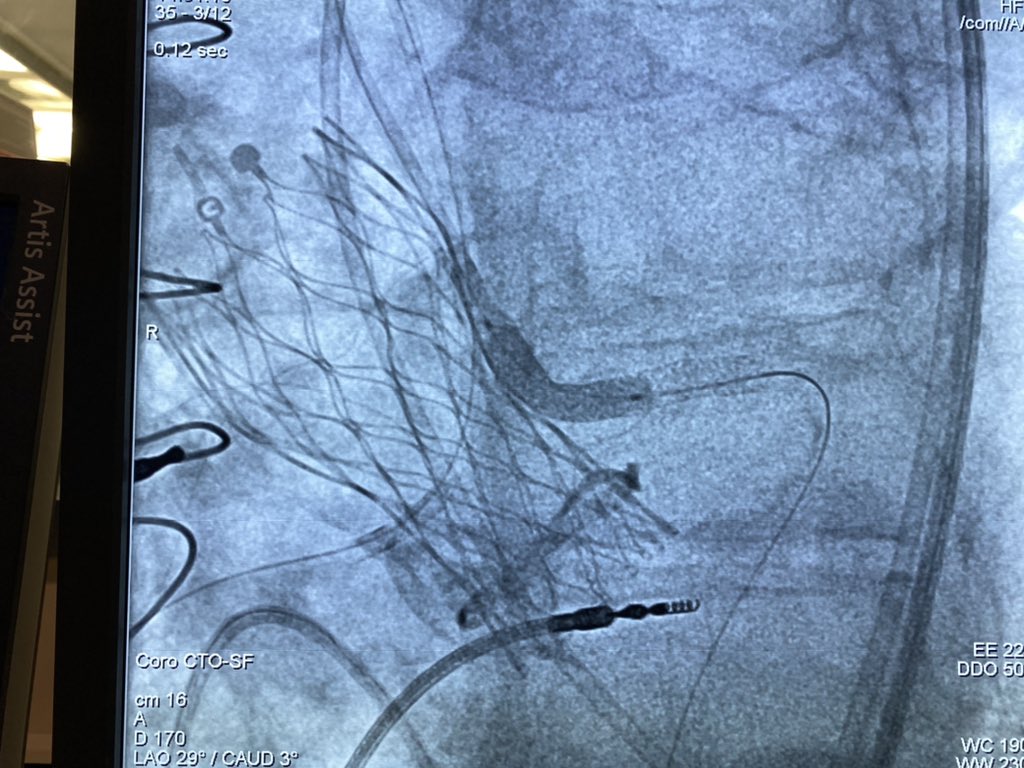

All our possibile tools to treat a severely calcified non crossable and non dilatable lesion: Rotablator, Shockwave and Guide Extension Catheter. Rimini Cath Lab.